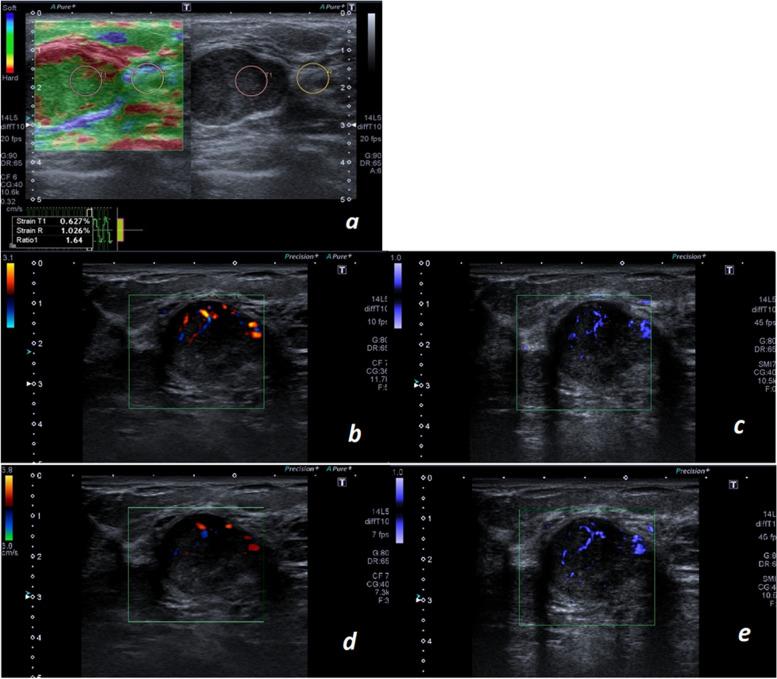

Breast ultrasound is highly sensitive, but its specificity is not as high for detecting malignant lesions. Auxiliary modalities like elastography, Color and Power Doppler ultrasound are used as adjuncts to yield both a high sensitivity and specificity. Superb microvascular imaging (SMI) is a newer modality with more accuracy for detecting breast lesions. In this study, our goal was to investigate the role of SMI as an adjunct to ultrasound and find a suitable combination model for the evaluation of breast masses.

METHODS

In this cross-sectional study, 132 women with 172 breast masses who underwent ultrasound-guided biopsy were included.. The ultrasound features of the lesion, the strain ratio in strain elastography, the number of vessels for each lesion, their morphology and distribution in Doppler and Power Doppler ultrasound and SMI were recorded for each lesion. A vascular score and a vascular ratio were defined.

RESULTS

In the histologic examination, 31 lesions (18%) were malignant and 141 lesions (82%) were benign. The vascular score was more accurate than the vascular ratio in all three modalities. The predictive ability of strain ratio was higher than Doppler and Power Doppler ultrasound and SMI. Adding SMI alone to ultrasound increased the specificity from 46.10% to 61.2% and the accuracy from 55.80% to 70.11%. In the combination of ultrasound with other modalities, the best was the combination of ultrasound, strain elastography, and SMI; which yielded a specificity and sensitivity of 100% and 74.4%, respectively.